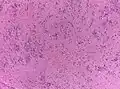

- Основным гистологическим типом является истинная эпендимома , для которой типично наличие периваскулярных и истинных «розеток». Периваскулярные «розетки» («псевдорозетки», «лучистая корона») состоят из клеток новообразования, которые располагаются вокруг кровеносных сосудов. В истинных «розетках» опухолевые клетки находятся вокруг каналов, которые выстланы эпендимарными клетками.

Кроме данных гистологических типов также выделяют злокачественный вариант эпендимомы — анапластическую эпендимому или эпендимобластому. Для данного типа характерны гистологические признаки анаплазии. При этой форме отмечается метастазирование опухолевых клеток по ликворным путям[2].